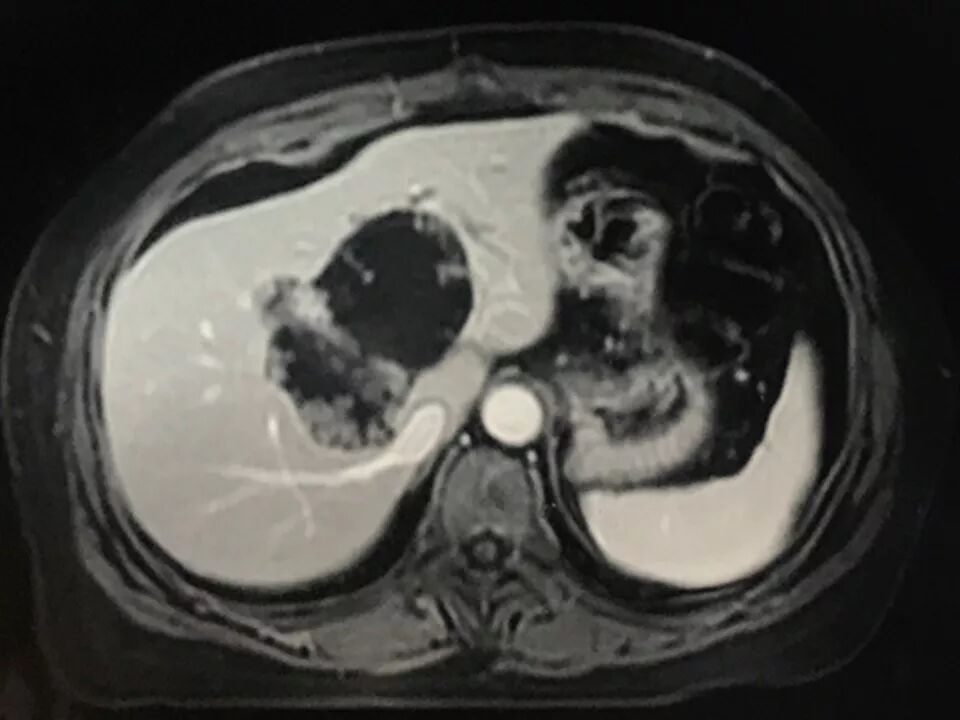

MRI表现:

肝内单发占位灶,累及肝左右叶及尾叶。T1WI示病灶以低信号为主,边缘多枚等信号结节,正反相位未见明显脂肪成份;T2WI示病灶以粘液成份为主呈高信号,边缘多枚稍高信号结节(相对肝实质),DWI呈不均匀等高信号,ADC图以高信号为主。动脉期病灶边缘均匀强化,壁结节显著强化,门脉期边缘仍持续强化,边缘光滑,壁结节呈相对等低信号。MRCP示胆管扩张,病灶与胆管相通。